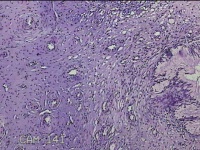

宫颈组织

性别

女

年龄

31岁

临床诊断

宫颈上皮内瘤变

一般病史

发现宫颈CIN2 2个月。

标本名称

大体所见

灰白暗红色组织2.8x1.8x0.3cm一块,表面糜烂,切面灰白暗红色,质软。

所提供图片不具有诊断价值。